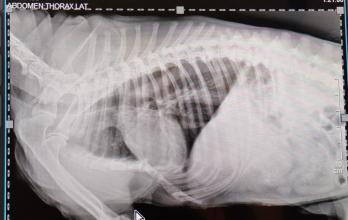

Le humectan los ojos con goteros que tienen componentes analgésico, le practican infusiones anestésicas para calmar de alguna forma el sufrimiento que siente. Tiene los pulmones dañados por la inhalación de humo y sus fosas nasales sangran por la inflamación. Se le dificulta respirar y se queja cuando lo hace. Por si fuera poco, luego de hacerle una radiografía se determinó que la perrita geriátrica tiene fracturas en las costillas y el esternón.